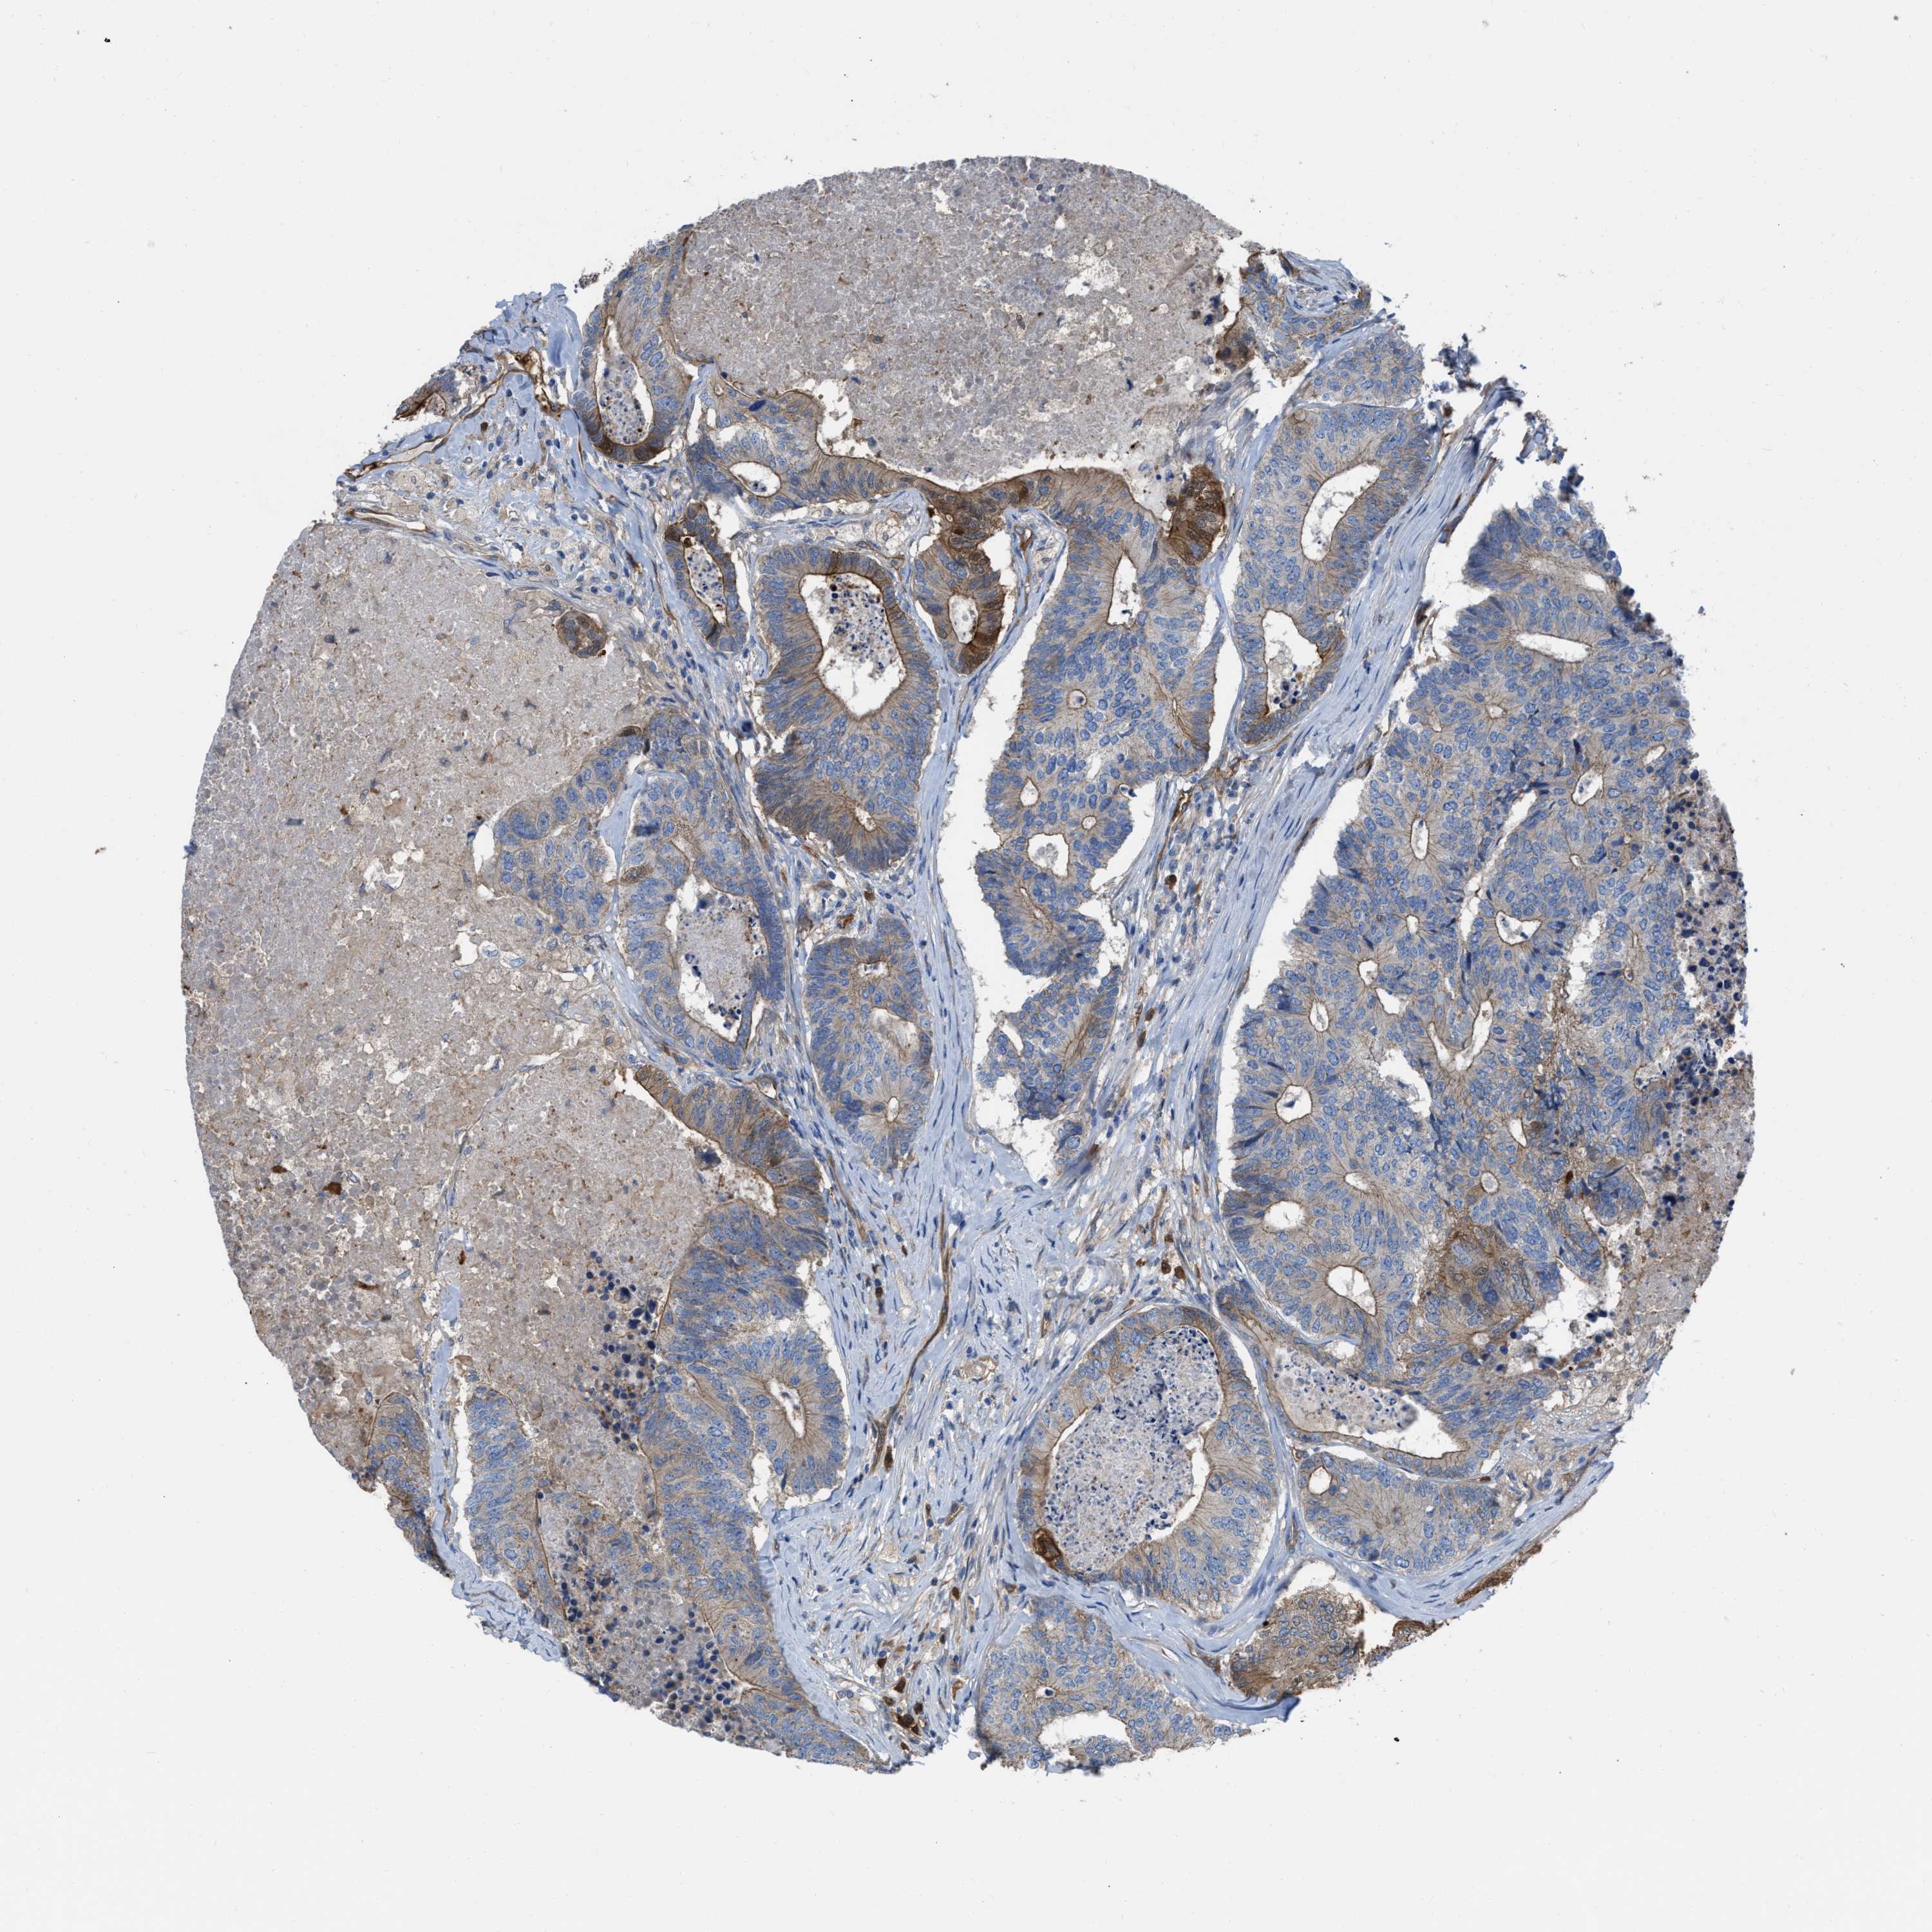

CANCER COLORECTAL CANCER Show tissue menu

Colorectal cancer

Human cancer

Colon adenocarcinoma

Rectum adenocarcinoma